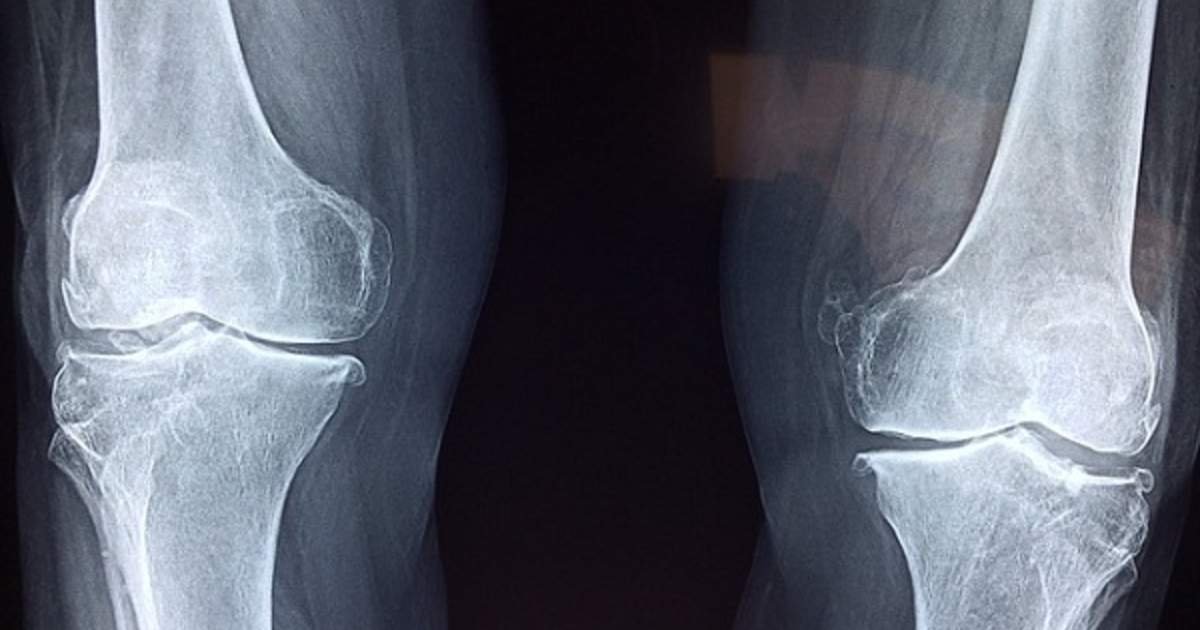

Age

Photo Credit: CranberryHomeCare

Individuals over the age of forty tend to develop chondrosarcoma more often than those who are younger. The best explanation for the prevalence in older aged adults has to do with mesenchymal stem and progenitor cells or MSPC. The cells that turn into chondrosarcomas are not clearly defined, but they most likely develop from the MSPC within the inside bone cavity. As an individual ages and the bones stop replacing their tissues as efficiently as they used to, the bones begin to undergo changes. The changes that occur can best be described as cell arrangement reorganization within the bones. Bone changes of this sort happen most prevalently among individuals in the beginning stages of osteoarthritis. The cell arrangement reorganization can change the bone and cartilage microenvironment, allowing for specific biomarkers to cause mutations in the DNA of MSPC. These mutations result in the genesis of chondrosarcoma. It is due to the normal bone changes that occur at older ages and the high prevalence of osteoarthritis that causes an individual over forty years old to be at a higher risk for developing chondrosarcoma.